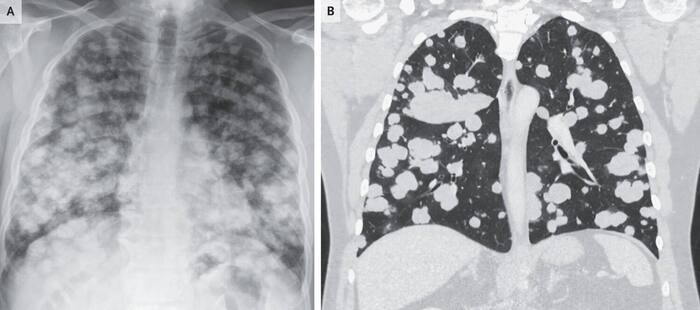

Поражение легких по типу «пушечного ядра» и рак яичек

В отделение неотложной помощи поступил 54-летний мужчина с легкой перемежающейся астмой, у которого в течение 2 месяцев усиливались одышка и кашель. Жизненные показатели были нормальными, а медицинский осмотр - ничем не примечательным. Рентгенограмма грудной клетки показала многочисленные круглые помутнения в обоих легких Фото А. Компьютерная томография грудной клетки выявила множество четко очерченных твердых узелков различных размеров в обоих легких - это явление известно как поражение легких “пушечным ядром” Фото В.

Поражения легких, напоминающие пушечные ядра, обычно указывают на гематогенное распространение рака на легкие. Эта рентгенологическая картина реже встречается при инфекционных или аутоиммунных заболеваниях. Лабораторные исследования показали, что уровень лактатдегидрогеназы составлял 5492 ед на литр (контрольный диапазон от 125 до 220), уровень бета-хорионического гонадотропина человека - 607 мкМЕ на миллилитр (контрольное значение ≤4,99), а уровень альфа-фетопротеина был в норме. Ультразвуковое исследование мошонки выявило образование в правом яичке. Была проведена бронхоскопия с эндобронхиальным ультразвуковым исследованием и трансбронхиальная пункционная биопсия легочного узла. На основании результатов гистопатологического исследования был поставлен диагноз метастатической эмбриональной карциномы, разновидности несеминоматозной опухоли из зародышевых клеток. Было проведено лечение химиотерапией на основе платины с последующей восстановительной химиотерапией. Пациент проходит обследование для трансплантации аутологичных стволовых клеток.